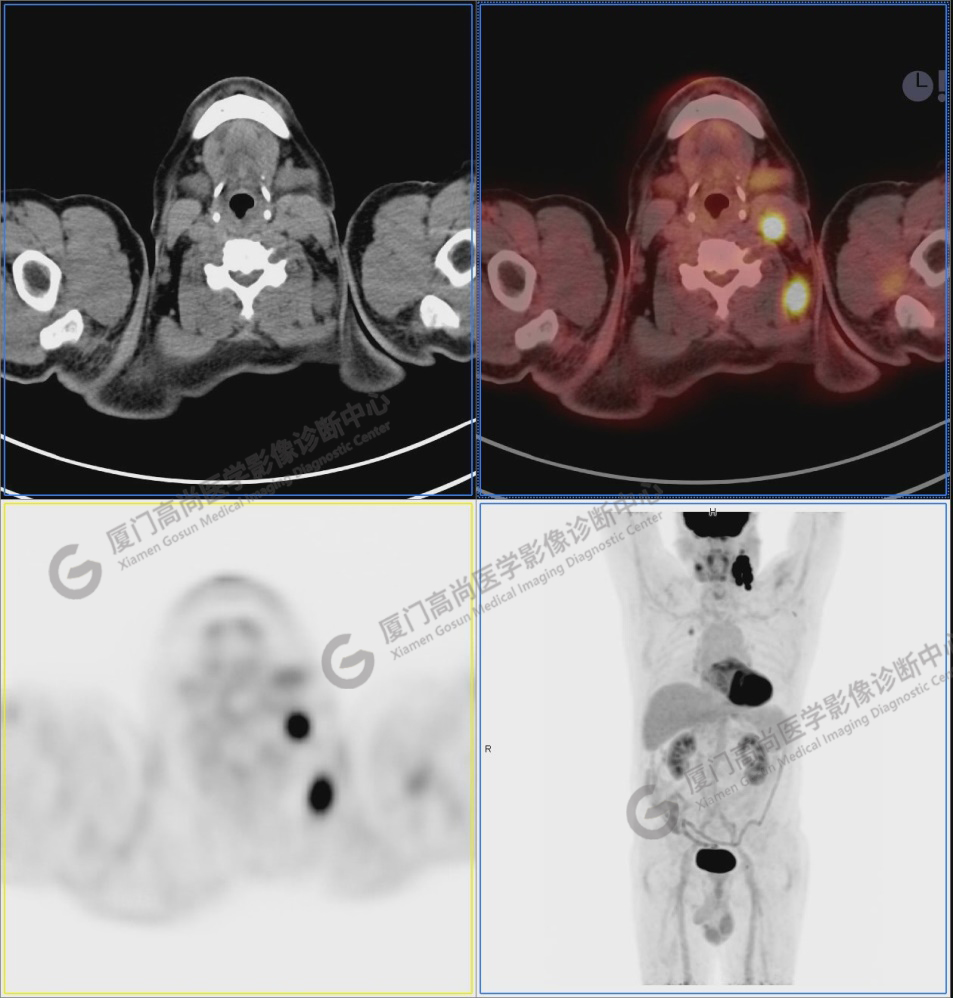

圖5

圖6-9:鼻咽左側(cè)壁增厚,代謝異常增高,考慮為鼻咽癌